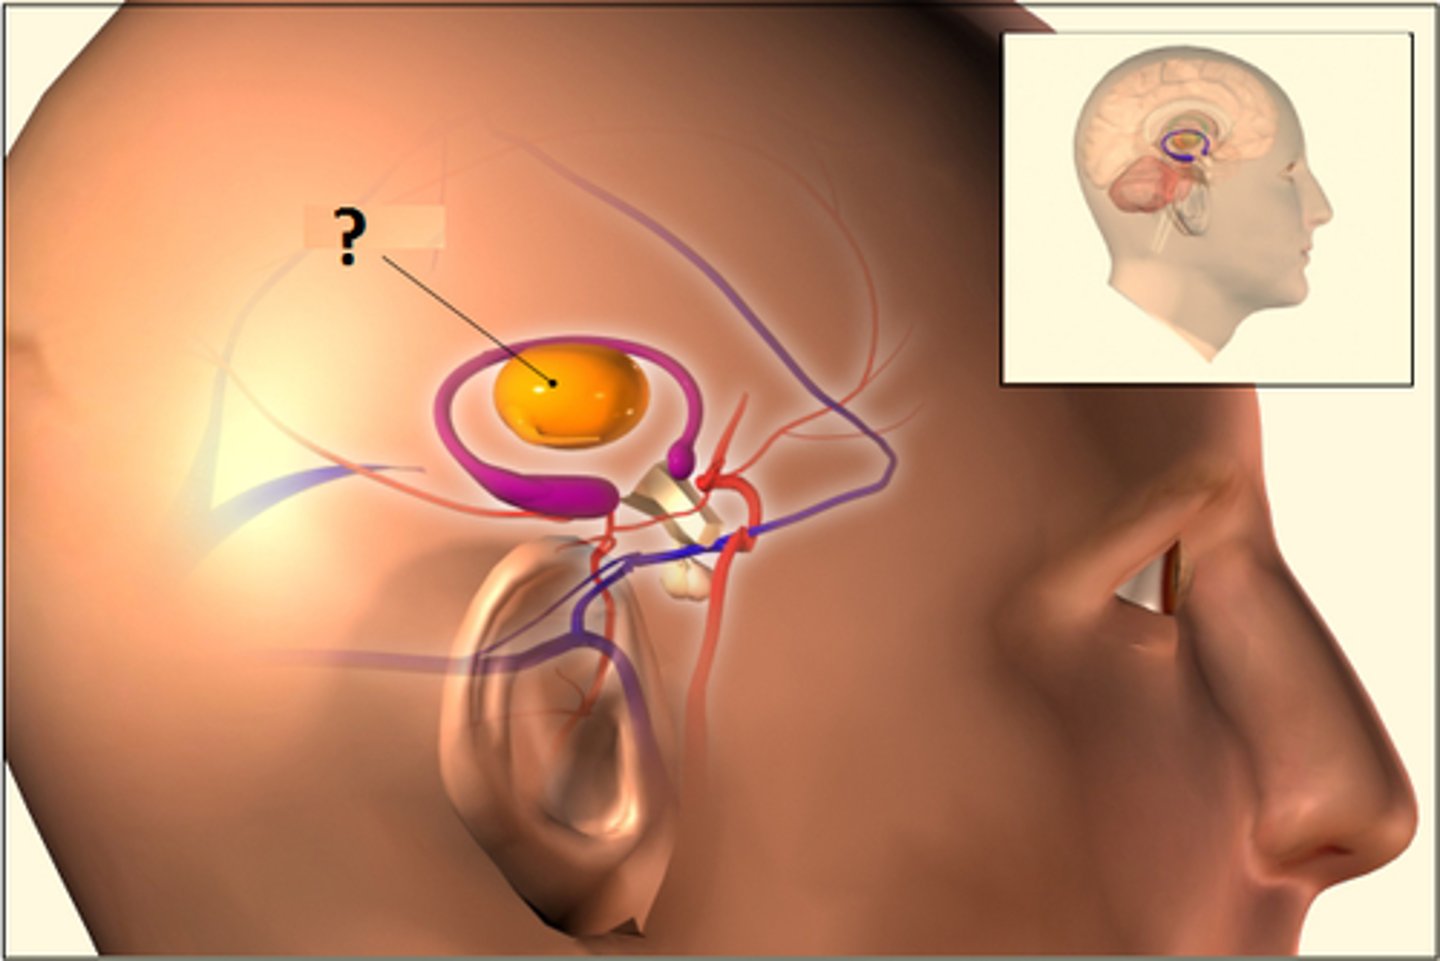

Limbic system

emotional center of brain that also plays roles in smell, motivation, and memory

Amyglada

part of limbic system involved in

fear, excitement, and arousal